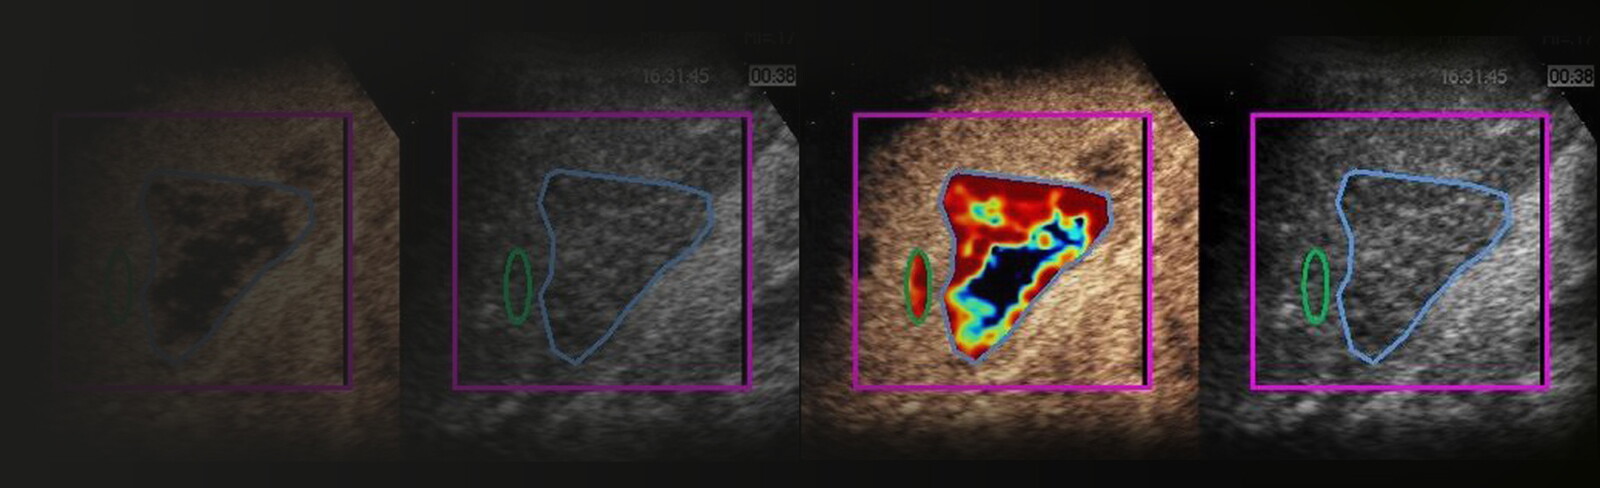

VueBox® Research is a quantification software designed to analyze DCE-US DICOM clips and is intended to be used in Research settings by trained physicians or researchers.

• Quantification of DCE-US sequences

• Obtaining accurate perfusion parameter values

• Export of the linearized experimental data and parametric images